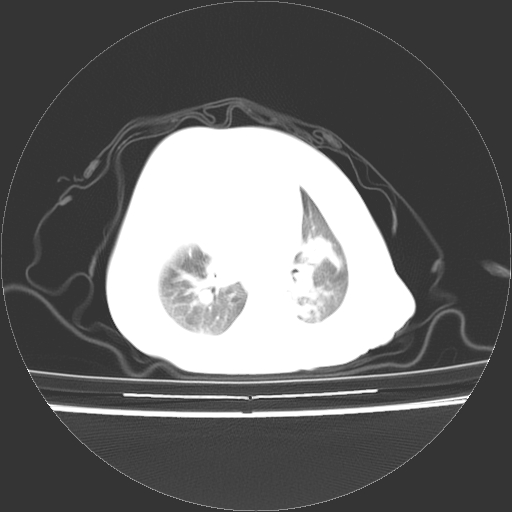

以下是引用影像之路在2009-5-8 15:46:00的发言:[br]1)胸廓畸形。2)考虑两肺感染性病变,并右肺上中叶肺不张;建议抗炎治疗后复查。3)胸腺肥大。4)前上中纵隔占位性病变待排;建议追踪复查。

以下是引用随光逐影在2009-5-8 8:33:00的发言:[br]1)胸廓畸形。2)考虑两肺感染性病变,并右肺上中叶肺不张;建议抗炎治疗后复查。3)胸腺肥大。4)前上中纵隔占位性病变待排;建议追踪复查。

以下是引用余辉在2009-5-8 8:44:00的发言:[br]鸡胸,胸腺肥大,双肺感染性病变,结合病史支原体肺炎可能性大